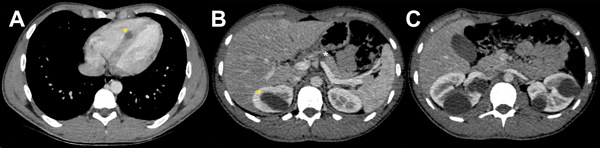

Se realizó tomografía computada de cuerpo completo que puso en evidencia múltiples lesiones quísticas cerebrales bilaterales, algunas de ellas en fosa posterior. Además, se hallaron lesiones cardíacas, dos de estas en el tabique interventricular, la mayor de 10 mm de diámetro. Otras dos se observaron en el ventrículo derecho y una más en el izquierdo. También se evidenció un quiste de 10 mm en el cuerpo del páncreas y múltiples lesiones renales bilaterales con diámetros de hasta 5 cm, de paredes gruesas y leve realce a la administración de contraste endovenoso. A nivel muscular se observaron imágenes similares en región cervical, lumbar, en ambos flancos y en el muslo izquierdo (Figura 1).

Figura 1. A) Corte axial de TC mediastinal con quiste en septum ventricular (asterisco amarillo). B) Misma secuencia a nivel abdominal donde se observan quiste pancreático (asterisco blanco) y renal (asterisco amarillo). C) Quistes renales bilaterales.